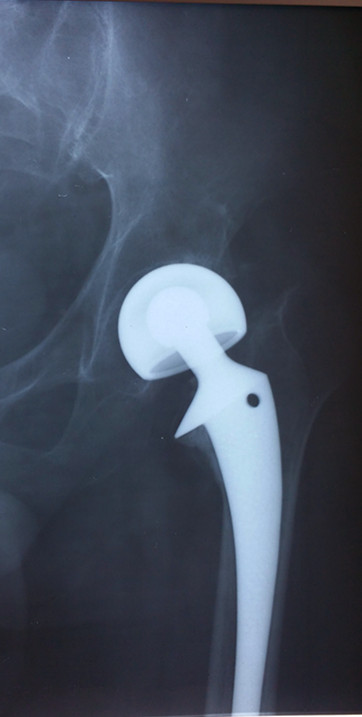

初次置换

患者宋先生,60岁,20年前在施工时不慎受伤,导致左髋部股骨颈骨折。在当地医院接受了“左侧人工股骨头置换”手术。7年前,患者再次受伤,导致左侧人工髋关节“假体周围骨折”。接受了“左人工髋关节二次翻修术”。1年前患者出现了左侧髋部慢性疼痛,半年前疼痛加重来我院就诊,X线检查提示“左人工髋关节假体松动下沉,周围骨质大片缺损”,诊断“人工髋关节术后感染”。